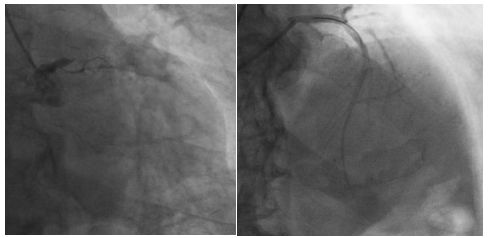

5月23日清晨,心内科主任医师胡江乔紧急会诊了这位67岁的急性广泛前壁心肌梗死患者,启动了胸痛绿色通道。心内科主任医师徐世莹、主治医师刘文博以最快的速度完成了冠脉造影检查,提示冠脉左主干100%闭塞。

心内科主任医师包恩泽面对挑战,迎难而上,在主动脉球囊反搏(IABP)循环支持及在大量血管活性药物维持生命体征下,指引导管到位、导丝顺利通过病变到达血管远段,球囊扩张,支架植入。从患者到达医院急诊至IABP置入、血管开通,仅用73分钟。患者左主干至前降支顺利植入2枚支架,胸痛明显减轻,生命体征逐渐平稳。

支架植入前 支架植入后